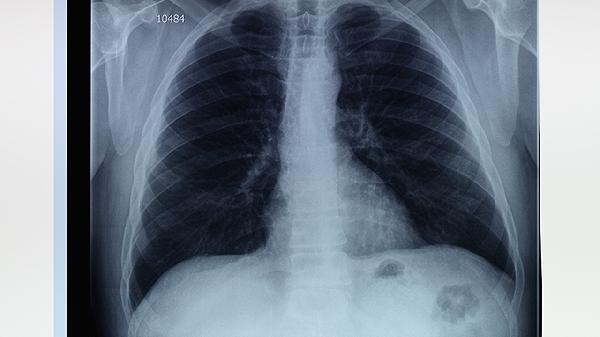

肺气肿并不等同于癌症,但两者都属于严重的健康问题,肺气肿是一种慢性肺部疾病,而癌症是细胞异常增殖的恶性疾病。肺气肿的主要特征是肺泡壁破坏,导致呼吸困难,而癌症则可能发生在身体的任何部位,具有侵袭性和转移性。肺气肿的治疗包括药物治疗、氧疗和肺康复,而癌症的治疗通常涉及手术、化疗和放疗。

肺气肿的发病与多种因素有关。遗传因素可能使某些人更容易患上肺气肿,例如α1-抗胰蛋白酶缺乏症。环境因素如长期吸烟、空气污染和职业性粉尘暴露是主要的外部诱因。生理因素包括年龄增长和肺部组织的自然退化。慢性支气管炎等病理因素也可能导致肺气肿的发生。

肺气肿和癌症虽然都是严重的健康问题,但它们的病因、病理机制和治疗方法截然不同。肺气肿患者应尽早戒烟、避免空气污染,并遵循医生的治疗建议。癌症患者则需要根据具体类型和分期制定个性化的治疗方案。无论是肺气肿还是癌症,早期诊断和干预都是改善预后的关键。